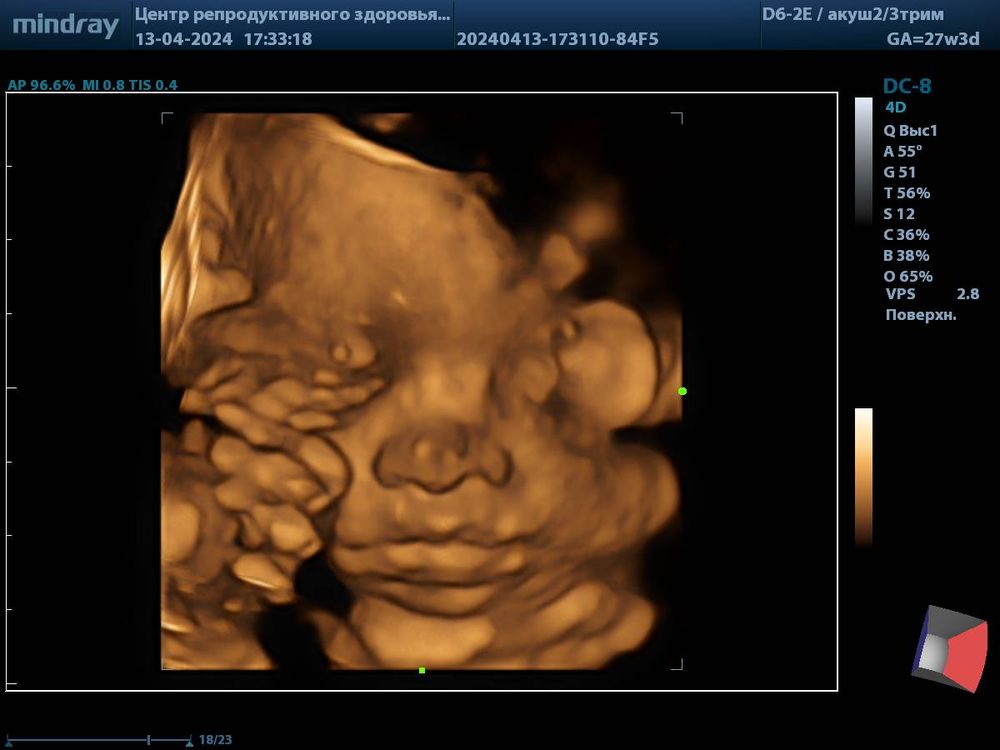

Сделала 3д, как хотела на память, правда она показалась всего на несколько мгновений, а потом ручками закрыла лицо и уперлась в плаценту) 26 мая ходила на фотосессию, очень интересно как получились фоточки 😍